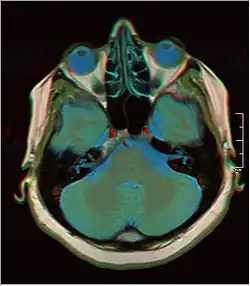

Normal axial T2-weighted MR image of the brain

Normal axial T2-weighted MR image of the brain -